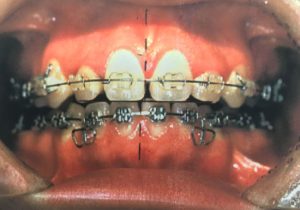

歯列矯正は超危険!全身に深刻な副作用のおそれ…食事や口の開閉が困難になる例も

歯にワイヤーを装着して歯並びを変える歯列矯正に副作用があることは、まだよく知られていませ...